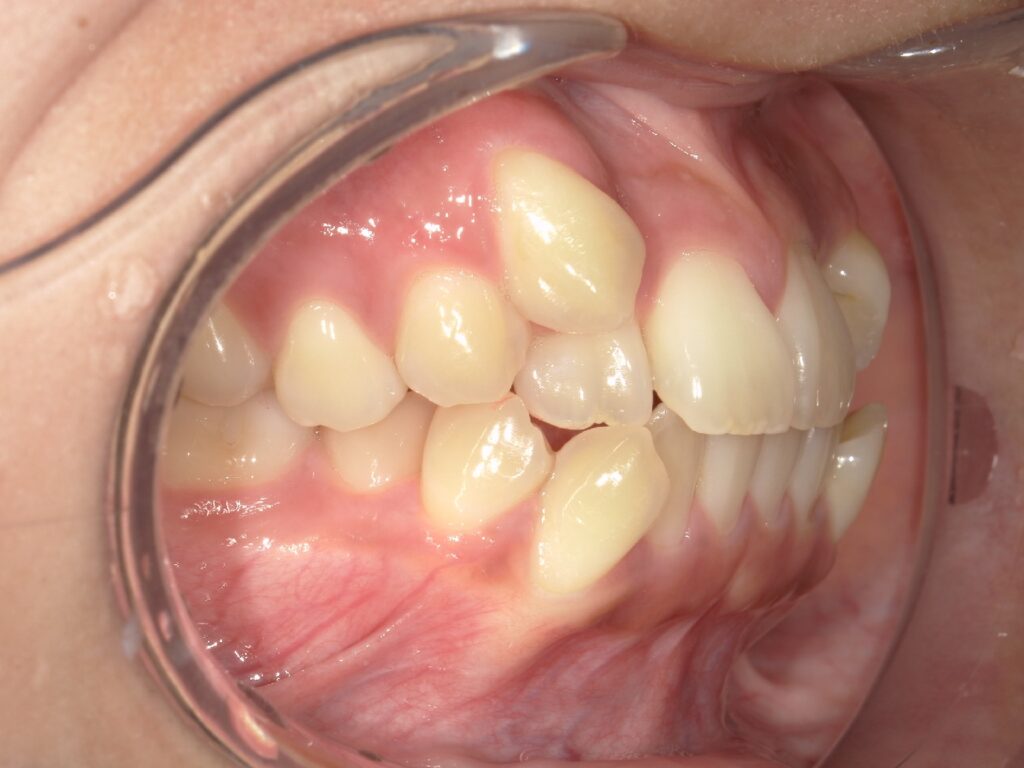

例えばこのケースは1年後の結婚式までにある程度歯並びをきれいにしたいとおっしゃって来られた患者様です。

矯正開始時

治療開始10ヶ月後

右上の八重歯はだいぶ改善して来たのですが、移動量が大きかったため、装置と歯との間に空隙を認めております。

これくらい浮きがある状態だと資料を撮り直して、新しい装置を作ることもありますが、それだと時間のロスになりますし、また結婚式には間に合いません。

そこで結婚式に少しでもいい状態で迎えていただくために、リカバリーでゴムかけを行いました。

下記が2ヶ月後の写真です。

治療開始1年後(治療途中です)

八重歯の部分がしっかり改善していることがわかります。

豊富な経験を積むことで、ズレがでてきた場合にすぐに新しい装置を作り直したほうがいいのか、それとも何かリカバリーをしたほうがいいのかを的確に判断することが無駄のない進行には、とても大切です。

この方は、この状態で結婚式を迎えることができましたので、とても喜んでいただきました。